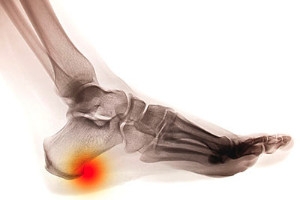

A common foot condition often associated with heel pain is referred to as a heel spur. A heel spur is a bony growth located as the name suggests, at the heel of the foot. They may form at the back of the heel, under the heel, or at the sole of the foot. Heel spurs can develop when the tendons and tissues that attach to the heel are overstretched or injured, often causing inflammation. Repetitive athletic stress and inflammatory diseases may also cause the development of a heel spur. Heel spurs may be diagnosed through the use of an ultrasound or X-ray in order to identify the bony protrusion. As far as treatment for heel spurs, it is suggested that you consult with a podiatrist for professional care and advice.

Heel spurs are the result of calcium deposits that cause bony protrusions on the underside of the heel. Heel spurs are usually painless, but they have the potential to cause heel pain. Heel spurs tend to be associated with plantar fasciitis, which is a condition that causes inflammation of the band of connective tissue that runs along the bottom of the foot. They most often occur to athletes whose sports involve a lot of running and jumping.

It is possible to have a heel spur without showing signs of any symptoms. However, if inflammation develops at the point of the spur’s formation, you may have pain while walking or running. In terms of diagnosis, sometimes all a doctor needs to know is that the patient is experiencing a sharp pain localized to the heel to diagnose a heel spur. Other times, an x-ray may be needed to confirm the presence of a heel spur.